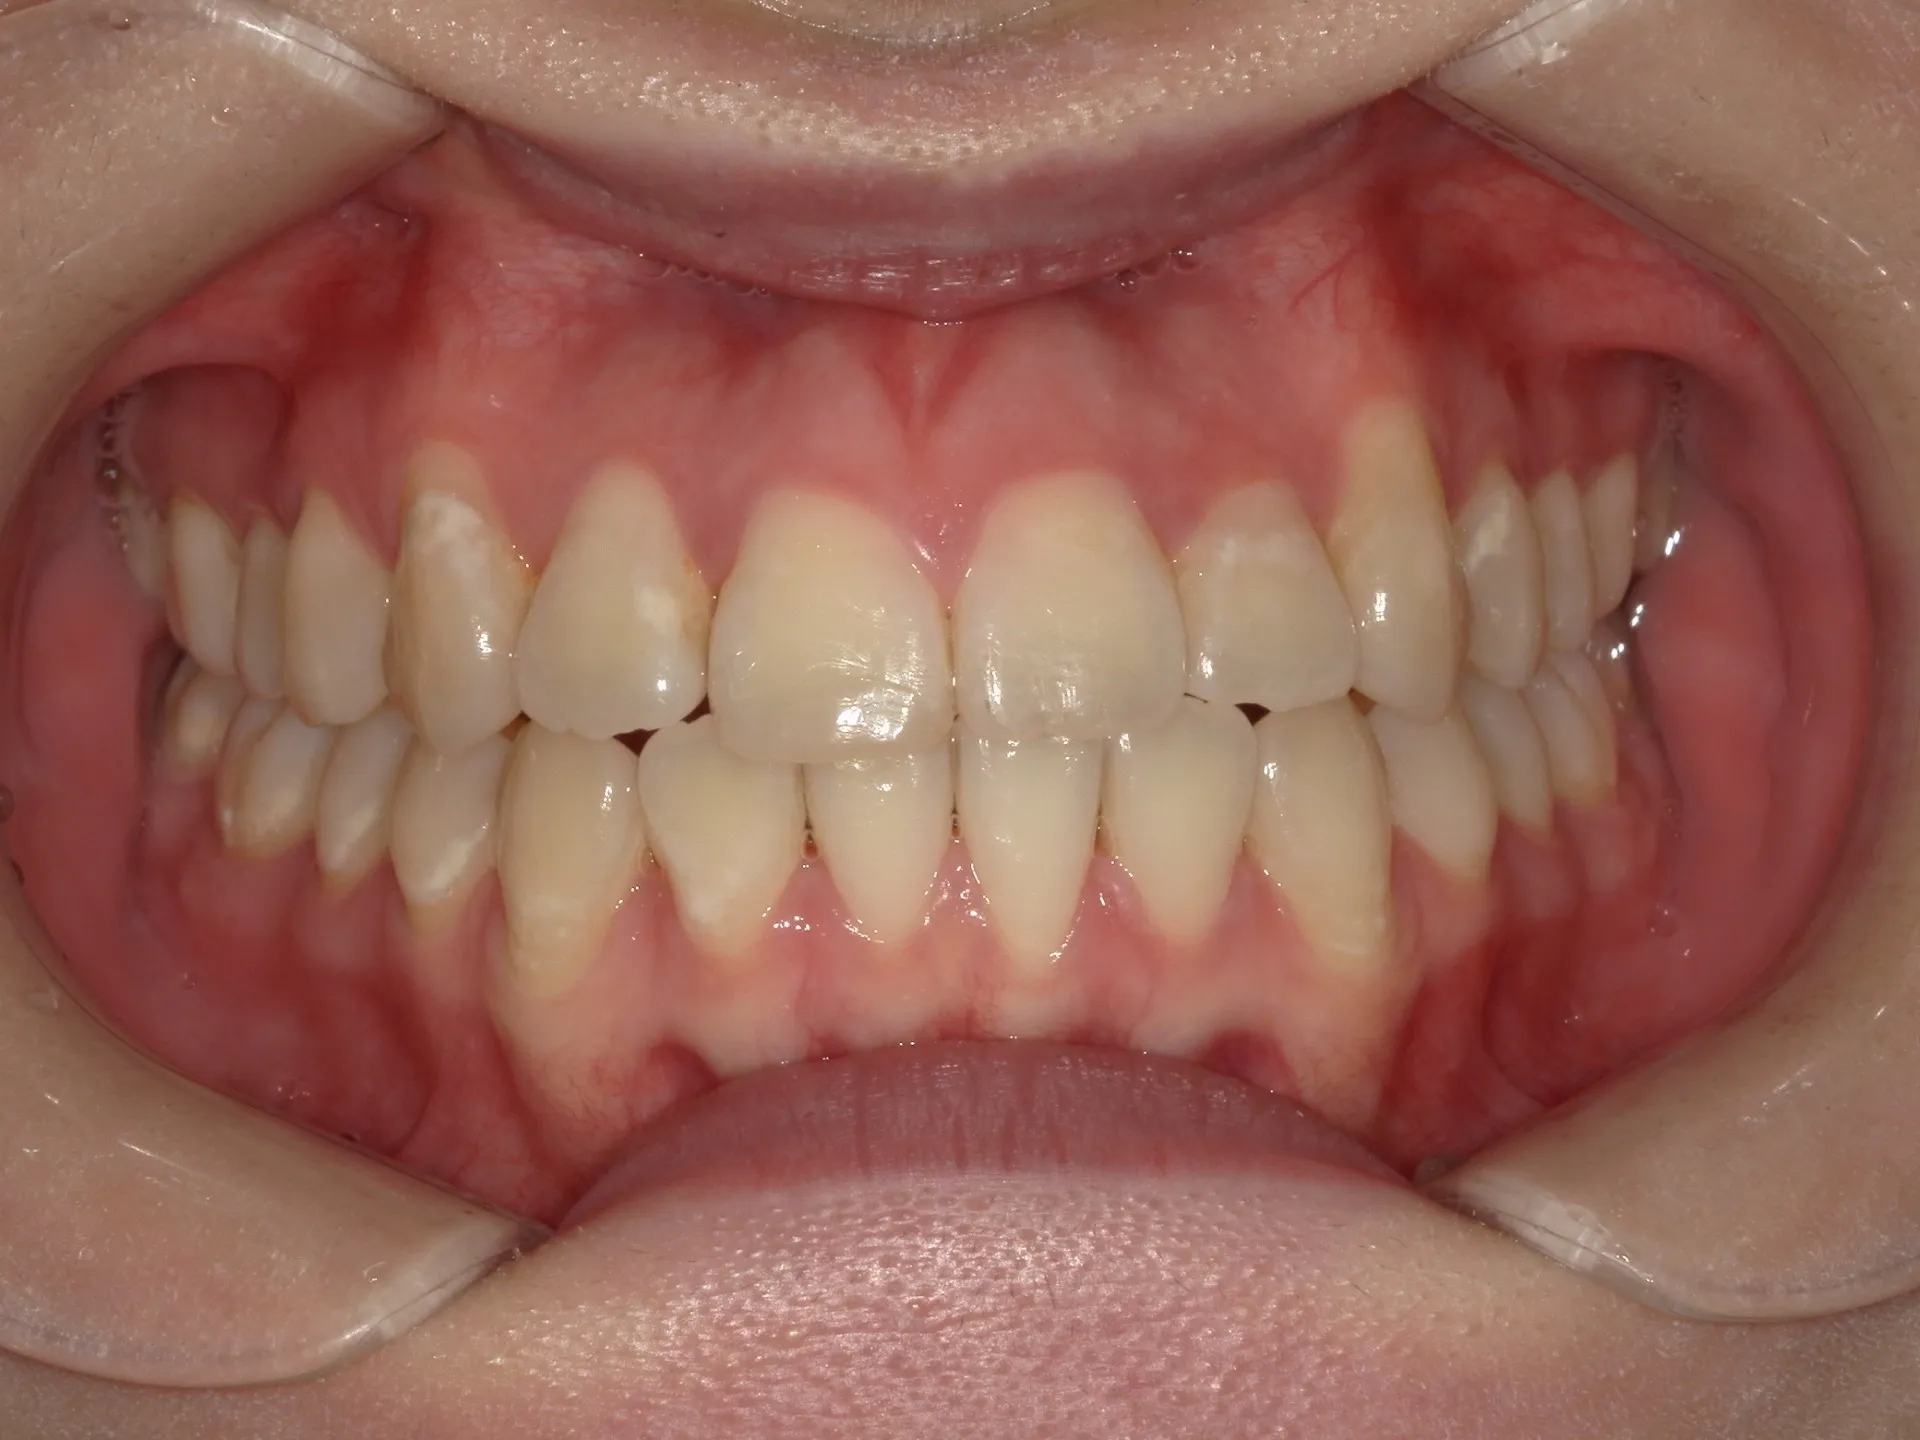

今回はマウスピース矯正で治療した八重歯の矯正についてご紹介いたします。

どこまでが軽度でどこまでが中等度のガタツキなのかにもよりますが、治療前の歯並びであれば患者さんの協力も当然必要ですが、マウスピース矯正でも十分治療できることが分かります。